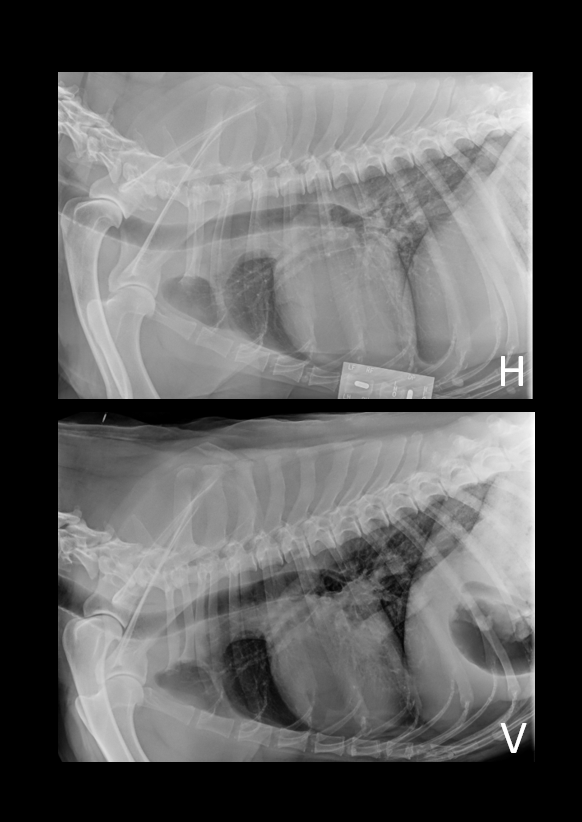

Denne gangen har vi lyst til å dele et kasus som vi syns er ganske interessant. Studien ble sendt inn til oss fra Dyrlegene i Skolestua, og sammen kom vi frem til en diagnose som kan forklare hundens problemer. Signalement: Pyreneerhund, tispe, 9år Anamnese: Eier syns hunden har blitt i dårligere form over tid, den bruker lang tid på å spise, tiltagende hosting. Eier har sau, så hunden jobber som vokterhund. Etter anstrengelse bruker hunden lang tid på restitusjon, peser lenge.